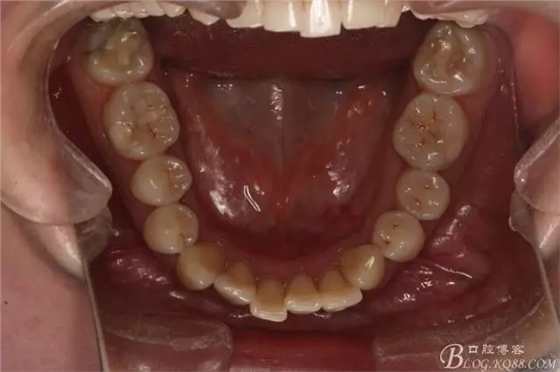

患者,女,主訴:牙齒不齊。

如圖,該病例為簡(jiǎn)單排齊病例,但77鎖合是矯治中的關(guān)鍵所在,你會(huì)怎么處理?